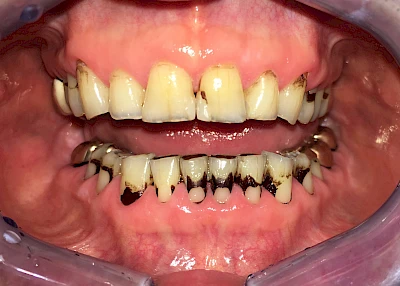

Gerade bei Kindern und Jugendlichen werden zunehmend häufiger bräunliche Verfärbungen mitunter auch mit Formveränderungen (die Oberfläche ist rauh oder zerklüftet) der Zähne beobachtet. Meist sind Schneidezähne oder Backenzähne betroffen. Dies könnte ein Hinweis auf sogenannte Kreidezähne (MIH: Molaren-Inzisiven-Hypomineralisation) sein.

Bräunliche Verfärbung

Manche Medikamente wie zum Beispiel das Antibiotikum Tetrazyklin kann bei Einnahme im Zeitfenster der Zahnentwicklung auch irreversibel in die Zahnsubstanz. eingelagert werden. Tetrazyklin verfärbt die jeweils betroffenen Zähne bläulich und sollte deshalb während der Schwangerschaft und bei Kindern nicht verordnet werden.

Daneben gibt es noch seltene genetisch bedingte Schmelz- bzw. Dentinbildungsstörungen (Amelogenesis imperfecta, Dentinogenesis imperfecta), die neben Verfärbungen vor allem auch durch Veränderungen der Oberflächenstrukturen auffallen. In diesen Fällen ist eine engmaschige Betreuung durch den Zahnarzt wichtig.